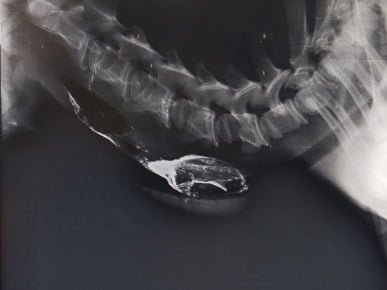

Veterinary Surgery and RadiologyStructures or organs can be evaluated more effectively for their size, shape and position by use of contrast radiography in animals.